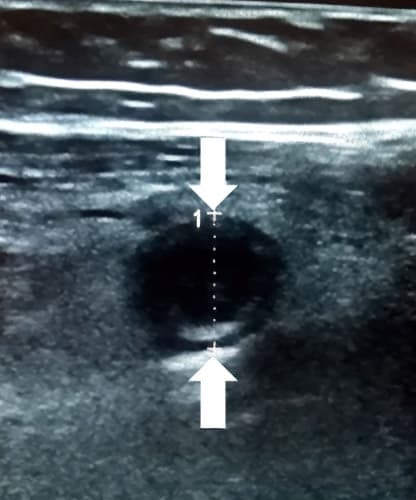

Каловые камни образуются из плотных каловых масс и неорганических солей. При УЗИ каловый камень выглядит как внутрипросветное гиперэхогенное образование с акустической тенью. Каловый камень в просвете воспаленного аппендикса часто сочетается с гангренозным аппендицитом (см. рис. 6).

Рисунок 6. Каловый камень в просвете аппендикса.